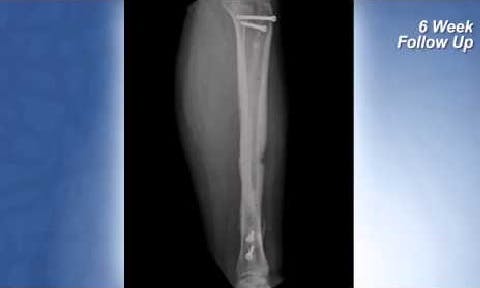

CASE STUDY Complex Tibia Fracture

See Dr. Joshua Niemann, M.D. explain the treatment and recovery of a motor vehicle accident trauma patient who received a tibial fracture plate composed of PEEK-OPTIMA Ultra-Reinforced